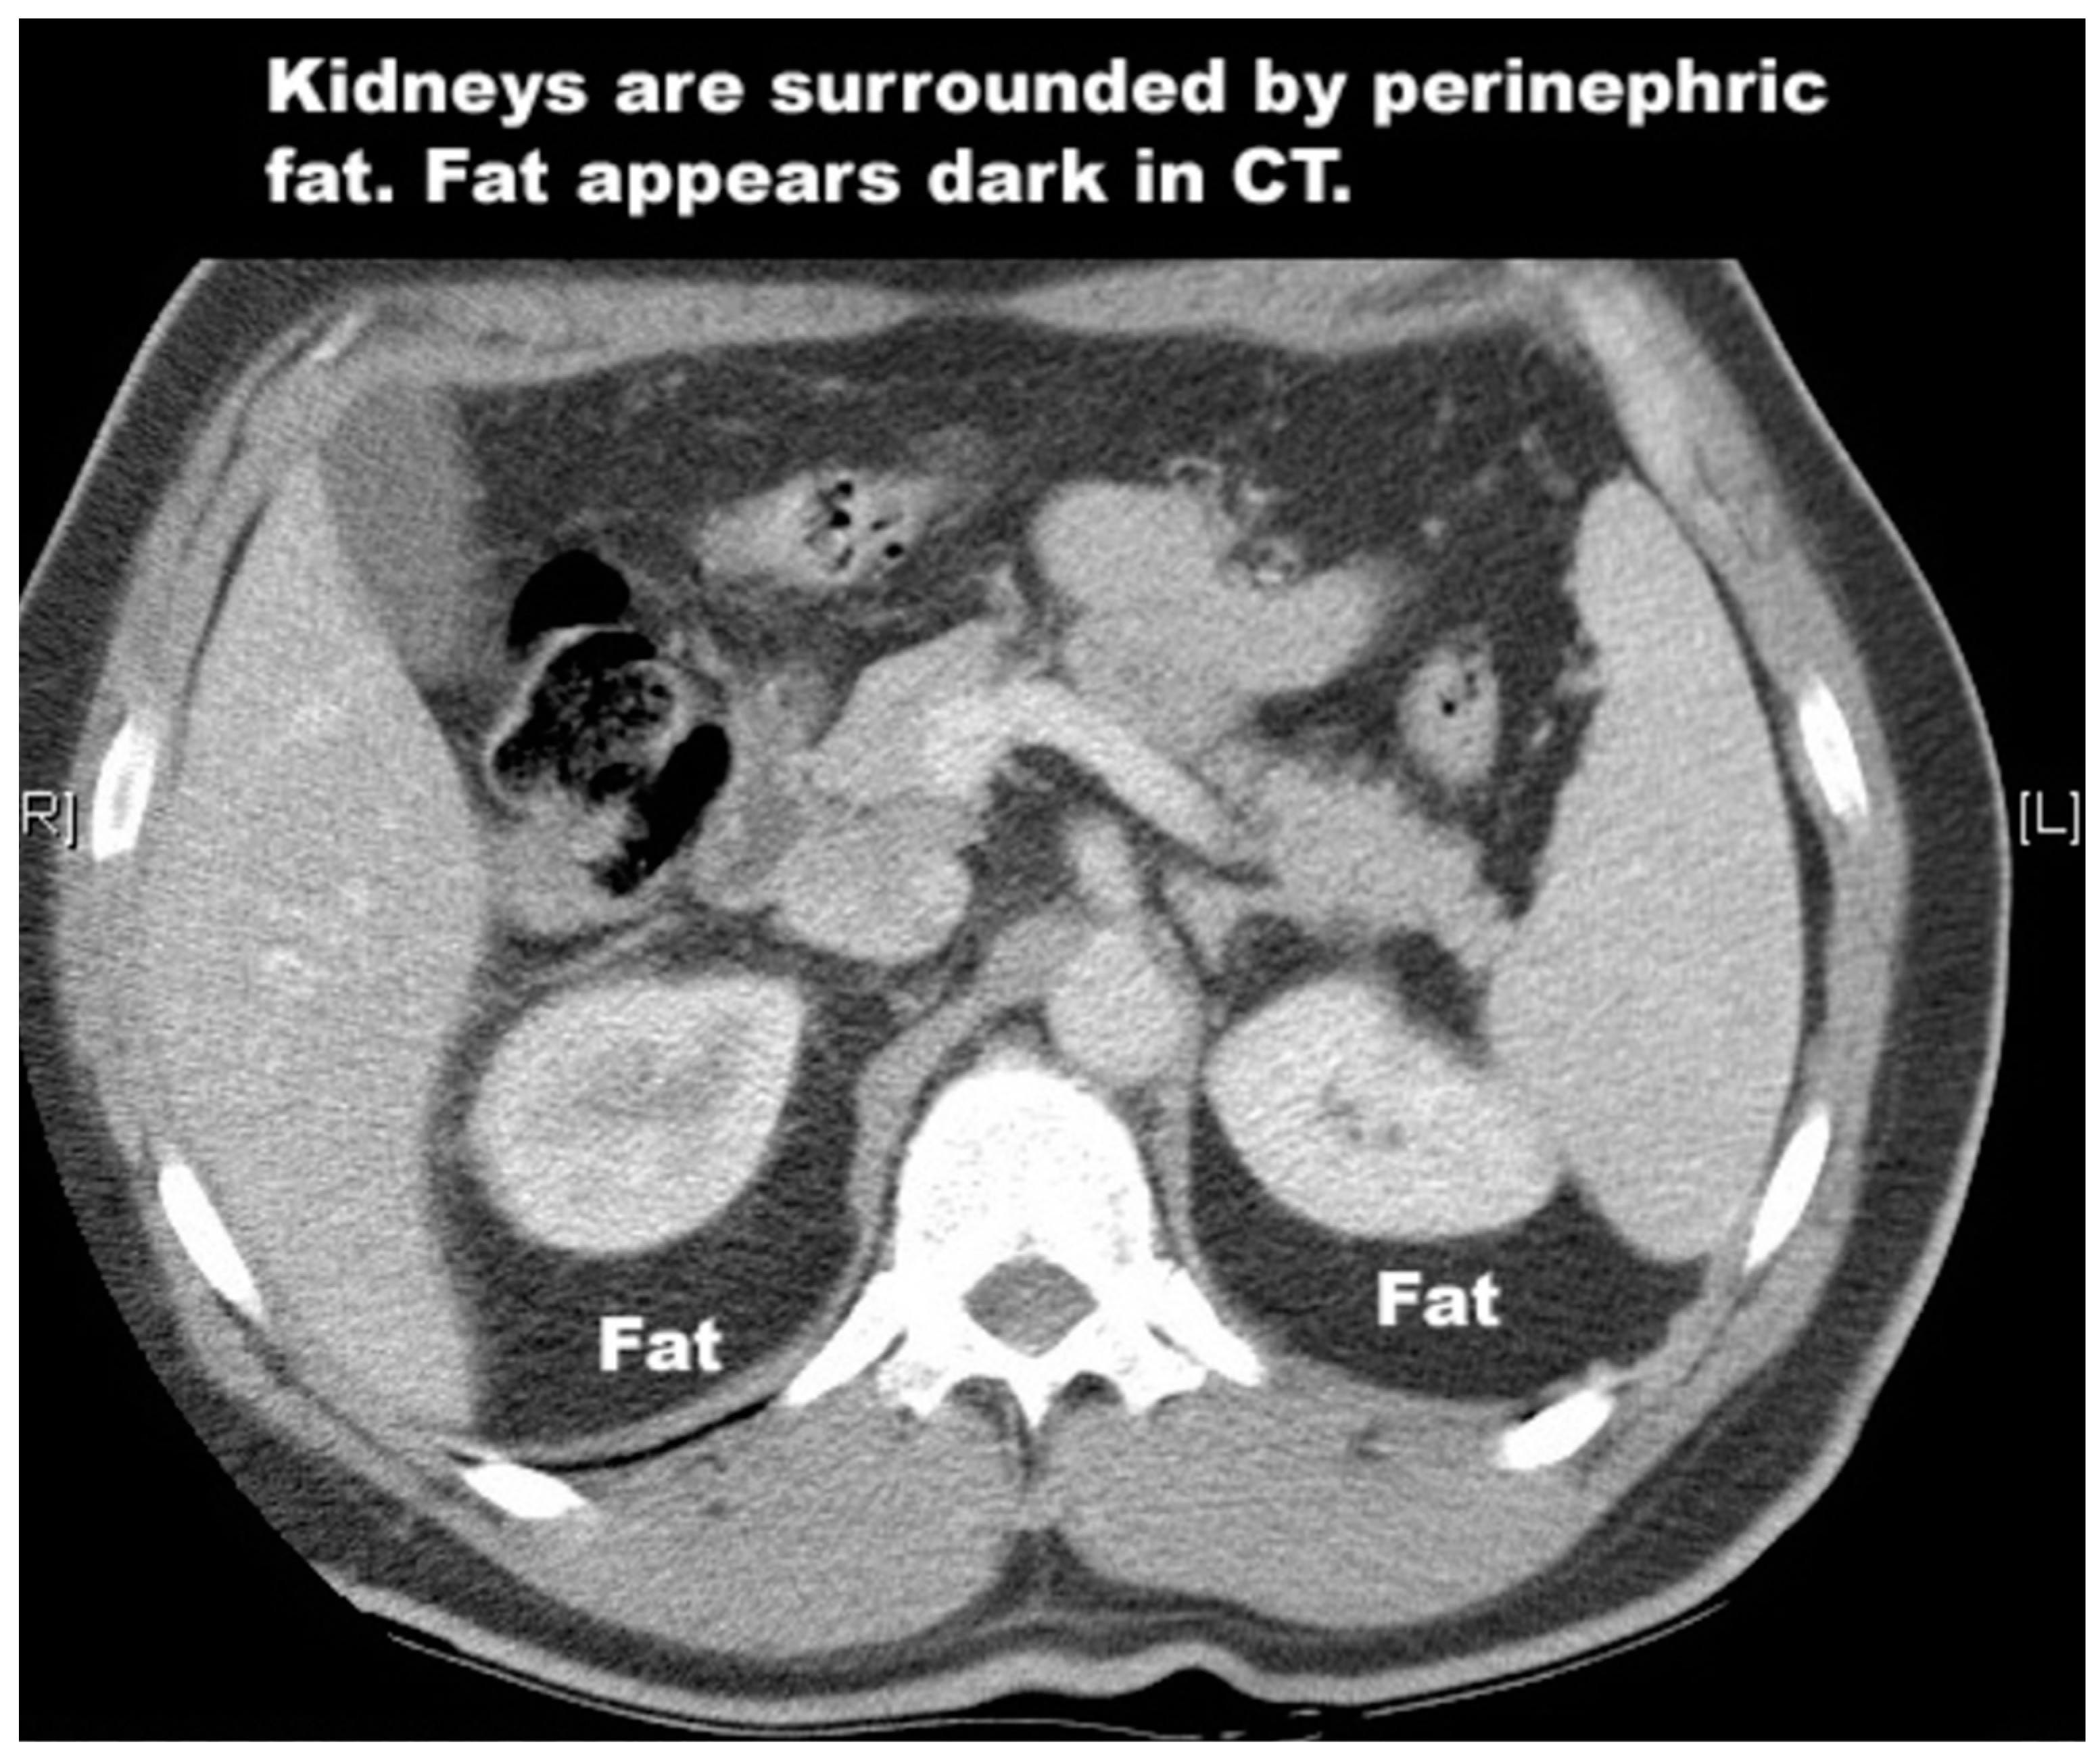

4.1. Kidney

- Ritchie, R.W.; Leslie, T.; Phillips, R.; Wu, F.; Illing, R.; Ter Haar, G.; Protheroe, A.; Cranston, D. Extracorporeal high intensity focused ultrasound for renal tumours: A 3-year follow-up. BJU Int. 2010, 106, 1004–1009. [Google Scholar] [CrossRef] [PubMed]

- Klingler, H.C.; Susani, M.; Seip, R.; Mauermann, J.; Sanghvi, N.; Marberger, M.J. A novel approach to energy ablative therapy of small renal tumours: Laparoscopic high-intensity focused ultrasound. Eur. Urol. 2008, 53, 810–816. [Google Scholar] [CrossRef]

- Illing, R.O.; Kennedy, J.E.; Wu, F.; Ter Haar, G.R.; Protheroe, A.S.; Friend, P.J.; Gleeson, F.V.; Cranston, D.W.; Phillips, R.R.; Middleton, M.R. The safety and feasibility of extracorporeal high-intensity focused ultrasound (HIFU) for the treatment of liver and kidney tumours in a Western population. Br. J. Cancer 2005, 93, 890–895. [Google Scholar] [CrossRef] [PubMed]